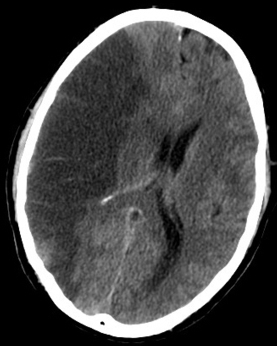

当流向大脑的血液中断,脑细胞缺氧时,就会发生中风。其后遗症包括肌肉无力和感觉障碍。在许多例子中,中风通常会影响患者的思考和处理信息的方式。

快速确定中风的影响有助于医生根据患者的需要制订康复计划。目前,神经影像学检查和神经心理测试可以发现认知损伤,但这些检查需要时间和患者的配合。